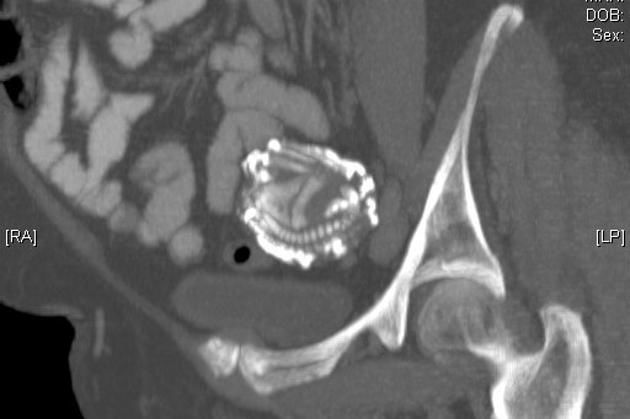

«Каменный ребенок», окаменелый плод, или литопедион (lithopaedion; греч. lithos камень + paidion ребенок), образуется в теле женщины в случае внутриутробной смерти плода. Организм воспринимает мертвое тело как инородное и, чтобы защитить себя от инфекции, покрывает его толстыми слоями кальция.

Литопедион может находиться в теле в течение долгих лет бессимптомно. Так, например, зарегистрирован случай, когда женщина 60 лет носила мертвый плод, не испытывая при этом никакого дискомфорта. Присутствие его обнаружили совершенно случайно, когда в госпитале она проходила медицинский осмотр. Именно так, случайно, литопедион, как правило, и находят — либо при прохождении медицинского осмотра, включающего в себя рентген органов брюшной полости, ультразвуковое исследование или томографию, либо во время операции.